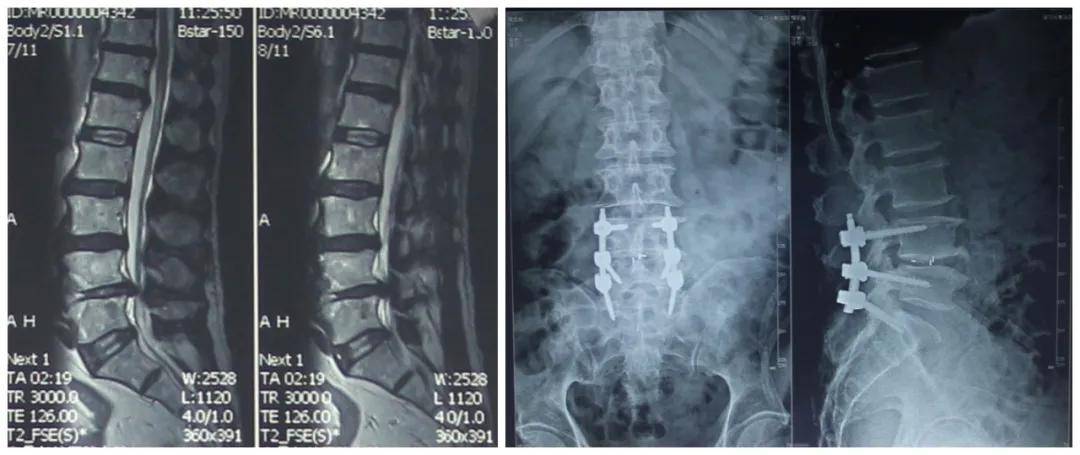

司法判例:腰椎间盘突出手术时内固定装置偏移,严重压迫患者神经【原告陈述】 2017年10月25日被告以“腰椎间盘突出症(L5-S)”将原告收治住院。2017年10月27日行手术,但在植入内固定装置时将位置偏移,致内固定装置对原告的腰5、骶1左侧神经形成严重压迫。术后,被告对原告进行拍片检查时仍未发现问题。 原告后于2017年11月22日出院...